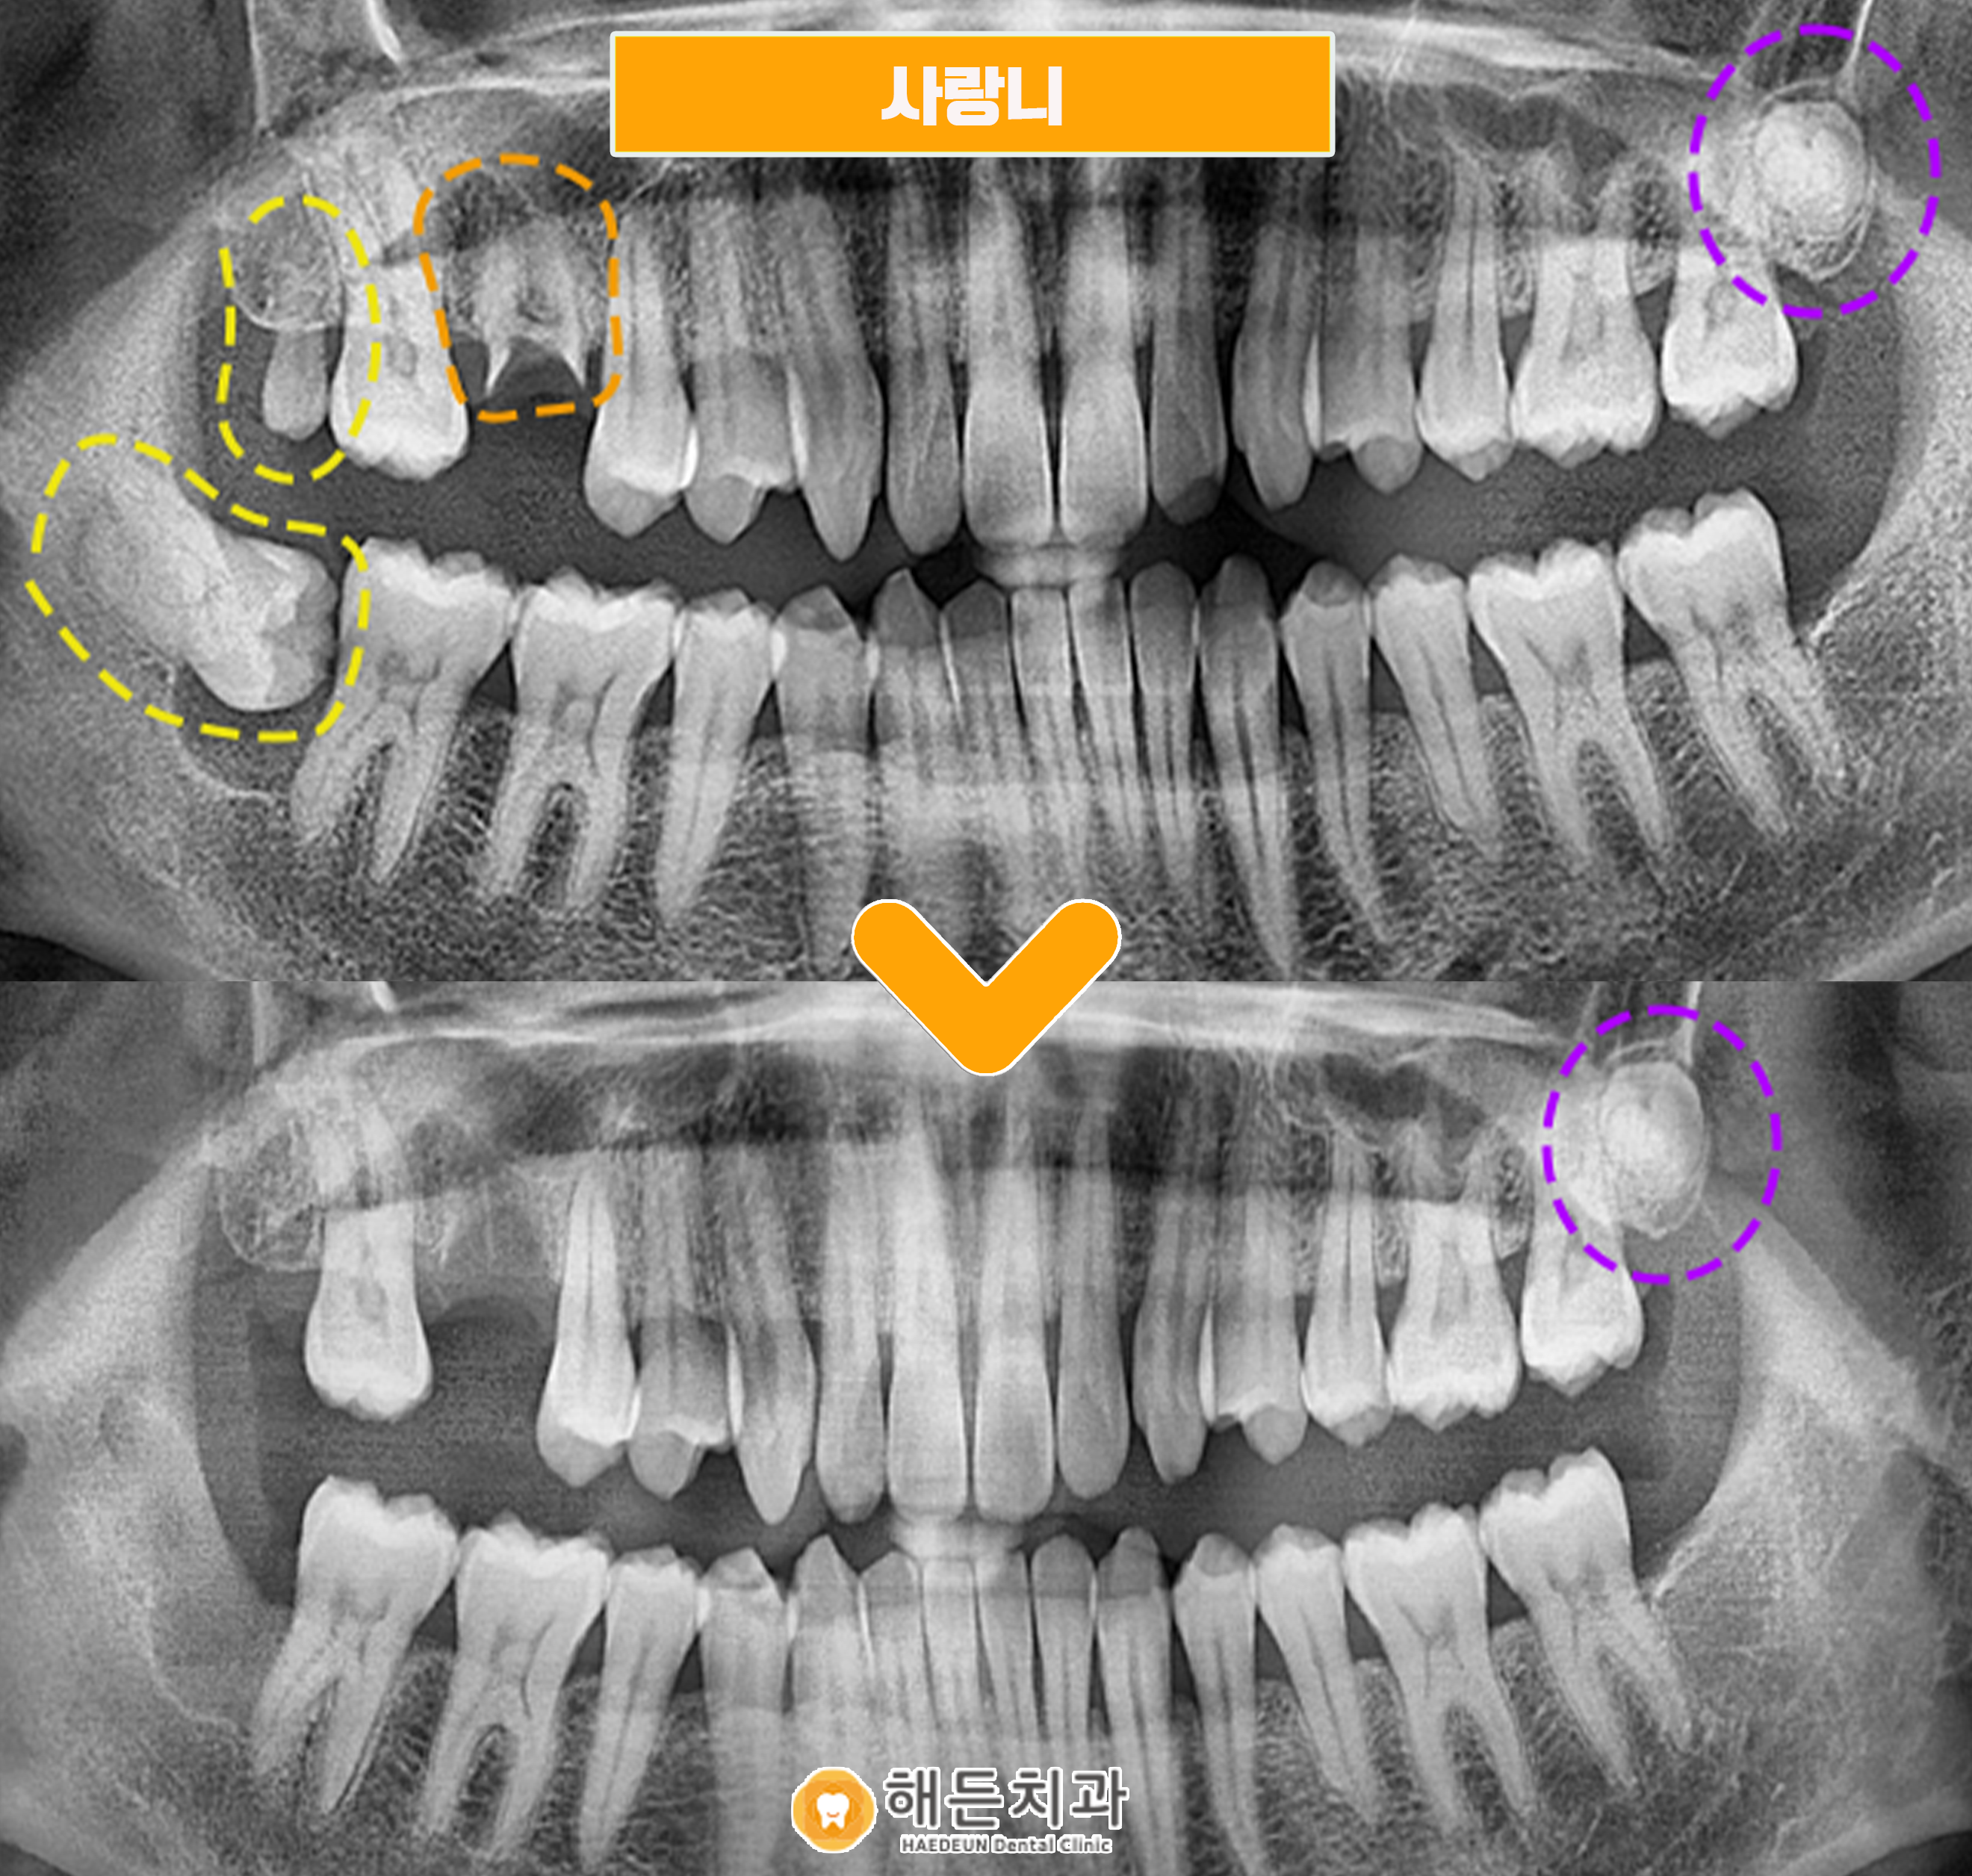

정밀한 검진을 위해 파노마라 사진을 촬영해 확인해보니,

현재 환자분의 구강 내에는 3개의 사랑니가 존재하고 있는 상태였습니다.

오른쪽 아래 사랑니는 완전히 기울어진 상태로, 구강 내 불편감을 주고 있는 상황이었으며,

오른쪽 위와 왼쪽 위의 사랑니는 다행히 크기가 작고 잇몸 위로 맹출되기 전이라, 환.자분께서 따로 불편감은 느끼지 않으신 상태였습니다.

우선은 불편감을 가지고 있는 오른쪽 아래 사랑니를 발치하면서

오른쪽 위의 사랑니와 주황색 표시의 뿌리만 잔존해있는 치아를 함께 발치를 도와드리기로 했습니다. 😊

사랑니 2개와 뿌리만 남아있는 치아, 총 3개의 치아가 뿌리 끝까지 깨끗하게 발치된 모습을 확인하실 수 있습니다.

아직 왼쪽 위의 사랑니는 잇몸 위로 맹출되지 않았으며,

환.자분께서 느끼는 불편감이 없는 상태라 추후 뽑으시기로 하셨답니다.